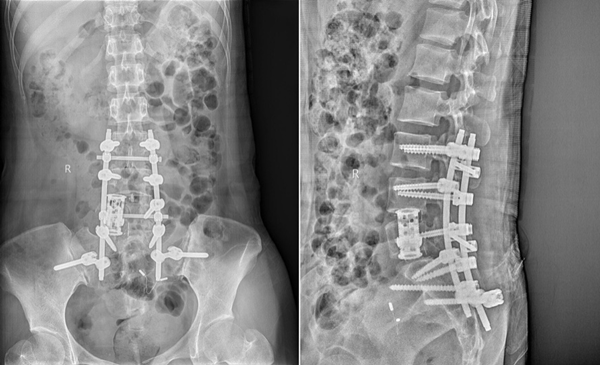

骨一科为腰椎巨大神经鞘瘤患者实施手术

近日,骨一科成功为一例“腰5椎体巨大神经鞘瘤”导致腰5椎体破坏及神经受压患者实施高难度前后联合入路腰椎肿瘤切除人工椎体重建钉棒内固定术。术前在党晓谦主任的全程指导下,樊立宏主任医师、宋启春主治医师通过与工程师多次协商、...